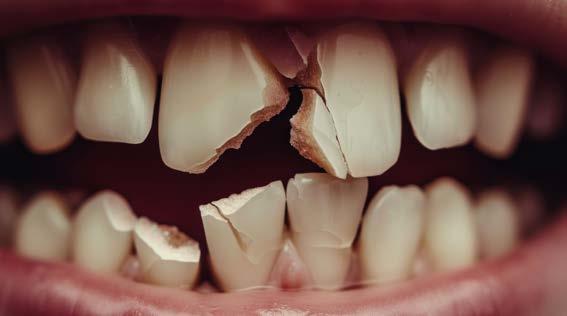

Figura 1. Se muestra una lesión extrusiva en los órganos dentales 21 y 22. Tomado de Aline Satie Takamiya y colaboradores en Iranian Endodontic Journal, Vol:4, Número:17, Año: 2022

Las lesiones traumáticas de los dientes permanentes son comunes y afectan entre el 10.5% y el 17.3%. La extrusión, la luxación lateral y la intrusión se encuentran entre los tipos más graves de traumatismo dental que pueden alterar el suministro vascular a la pulpa. Radiográficamente, las partes apical y lateral del alvéolo parecen vacías y, en general, el espacio del ligamento periodontal está agrandado. La obliteración del canal pulpar (OCP) y la necrosis pulpar (NP) son las consecuencias más frecuentes de la luxación extrusiva, mientras que la reabsorción radicular (RR) es menos frecuente. Las complicaciones dependen de factores como la gravedad de la lesión, el estadio de desarrollo radicular y la presencia de una alta carga bacteriana bucal. Las complicaciones pulpares y periodontales son más frecuentes en dientes con raíces completamente formadas que en ápice abierto. La prevalencia de obliteración del canal pulpar (OCP) como consecuencia de lesiones por avulsión y luxación está entre el 3 y el 24%. Por el contrario, es muy poco probable que los dientes con ápice cerrado presenten revascularización y a menudo desarrollan

Figura 2. Imagen representativa de una luxación extrusiva en el órgano dental 11 que presenta un cambio de coloración en la encía.

necrosis pulpar. Las lesiones por luxación extrusiva requieren un tratamiento inmediato, consistente en reposicionamiento y estabilización. El tratamiento comienza con un correcto diagnóstico clínico y radiográfico, seguido del reposicionamiento manual del diente en el alvéolo y la colocación de una férula flexible, para permanecer in situ durante aproximadamente 2 semanas.6